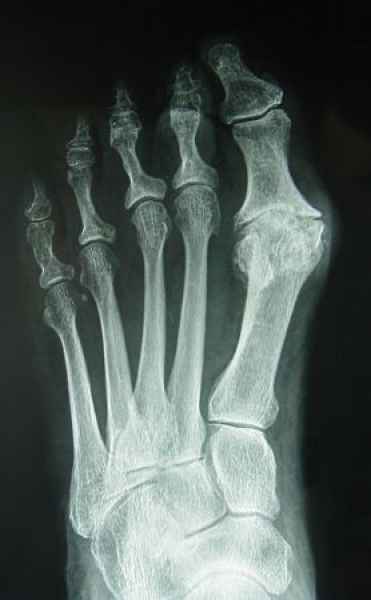

El pie es el órgano distintivo y característico de la especie humana, la única criatura que marcha erguida. El pie es una muy compleja estructura de arquitectura perfecta, adaptado a su función de apoyo, traslación, salto, con una riquísima sensibilidad que le permite detectar las más leves imperfecciones del suelo para estabilizar la marcha.

La marcha no solo es característica de la especie humana sino también de cada persona, y más aún varía según el estado de ánimo del momento. Una patología en los pies, se traduce en el rostro, en el ánimo, en el psiquismo. No sólo el dolor produce estos efectos, también un pie deformado o poco estético. En nuestra sociedad, la estética constituye un valor muy apreciado y estas alteraciones causan vergüenza fundamentalmente en las mujeres, que esconden en la playa sus pies en la arena y no pueden usar calzados elegantes.

Tanto la estructura del pie como su funcionalismo que es la marcha, pueden ser asiento y manifestación respectivamente de alteraciones locales ó sistémicas, por lo que su cuidadoso examen resulta de extrema utilidad diagnóstica.